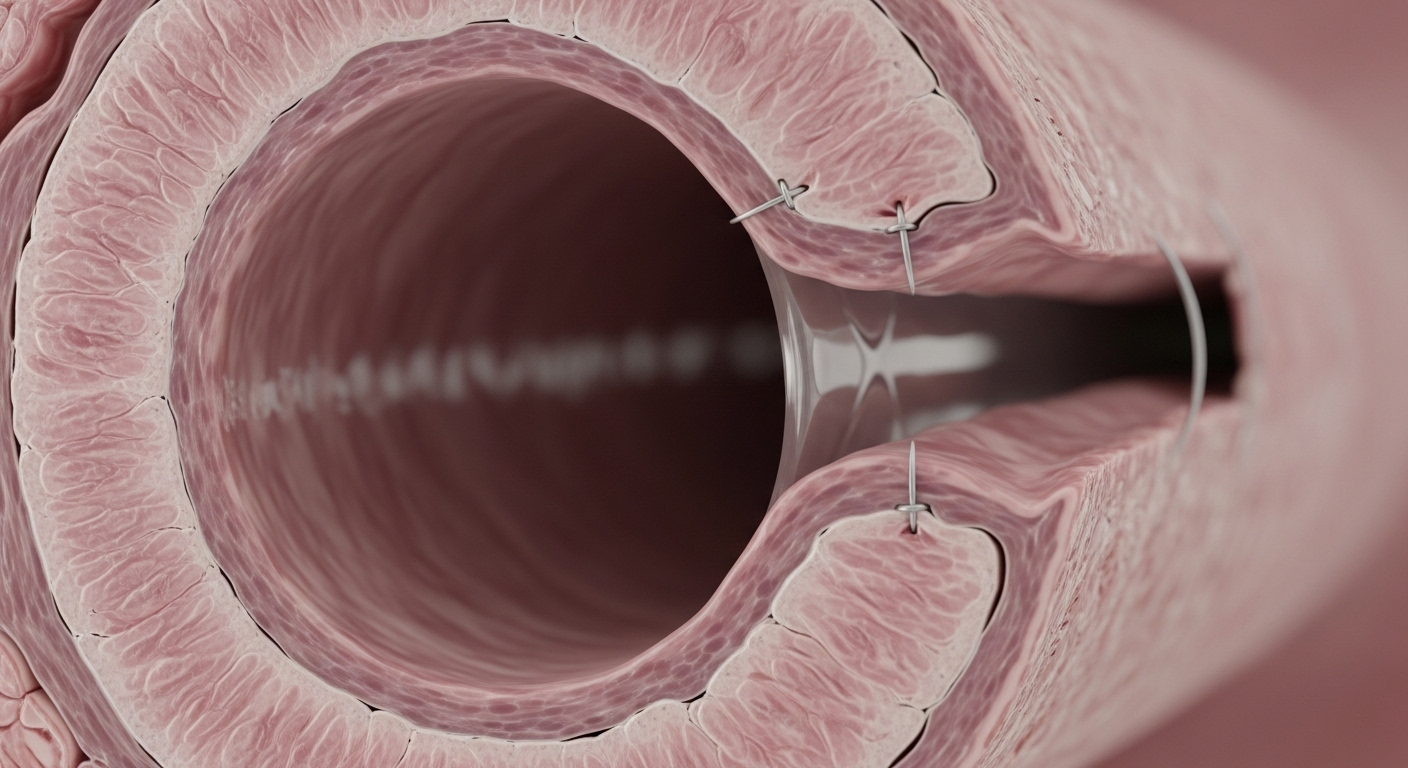

Phẫu thuật cắt đoạn nối tận: Kỹ thuật này được áp dụng khi đoạn phế quản bị hẹp không quá dài và nằm ở vị trí thuận lợi. Bác sĩ sẽ cắt bỏ phần phế quản bị tổn thương, sau đó khâu nối hai đầu phế quản khỏe mạnh lại với nhau.

Phẫu thuật tạo hình, trượt phế quản (Slide Tracheoplasty/Bronchoplasty): Đây là một kỹ thuật nâng cao, thường được dùng cho những đoạn hẹp dài hoặc hẹp khít rất phức tạp. Phẫu thuật viên sẽ cắt dọc phế quản theo một cách đặc biệt, sau đó trượt chồng hai đoạn phế quản lên nhau và khâu lại, tạo thành một đường thở rộng hơn đáng kể. Kỹ thuật này đòi hỏi trình độ phẫu thuật viên cực kỳ cao và trang thiết bị hỗ trợ hiện đại.

Đặt stent nội phế quản: Đây là một phương pháp ít xâm lấn hơn, thường được cân nhắc cho những trường hợp bệnh nhân không đủ điều kiện phẫu thuật lớn hoặc như một giải pháp tạm thời. Một ống lưới nhỏ (stent) sẽ được đặt vào lòng phế quản để giữ cho đường thở luôn mở rộng.

Kỹ thuật khâu nối tinh vi: Việc khâu nối các đoạn phế quản cần độ chính xác cực kỳ cao, đảm bảo đường thở mở rộng tối đa và tránh các biến chứng như rò rỉ tại chỗ khâu, hoặc tái hẹp sau này.